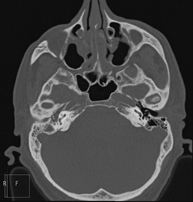

- TC Oídos

Prueba radiológica que consiste en obtener imágenes del oído de alta definición anatómica (conducto auditivo interno y externo, tímpano, huesecillos del oído), mediante el empleo de un equipo de TC (Tomografía Computarizada). Indicaciones: trastornos de la audición, cuadros vertiginosos, mareos, acúfenos (pitidos).

- TC Peñascos

Prueba radiológica que consiste en obtener imágenes del hueso peñasco del temporal (oído interno, medio y externo) de alta definición anatómica mediante el empleo de un equipo de TC (Tomografía Computarizada). Indicaciones: pérdida de audición súbita o crónica, cuadros vertiginosos, mareo, malformaciones congénitas.